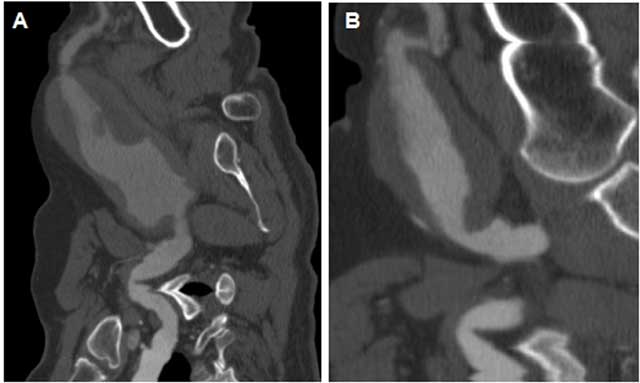

Figure 3

On a CT angiogram, bilateral axillary artery aneurysms were detected on curvilinear reformatted sections. (A) right, (B) Left.